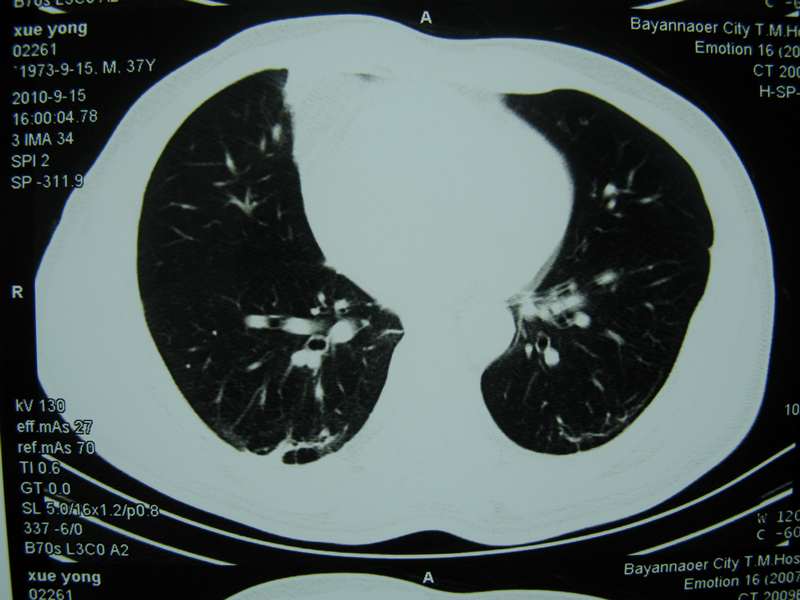

男,37岁,主述胸疼厉害,无咳嗽,无发热,血象也不高,病灶内ct值脂肪密度,右侧胸腔内少量积液,同道们考虑什么?谢谢!

脂肪垫,右下肺感染,少许积液是症状所在

两肺下叶基底段纤维灶,右肺下叶基底背侧相应胸膜肥厚,右肺中叶内侧段部分不张。前中下纵隔团块状脂肪影,随访除外胸腺脂肪瘤。